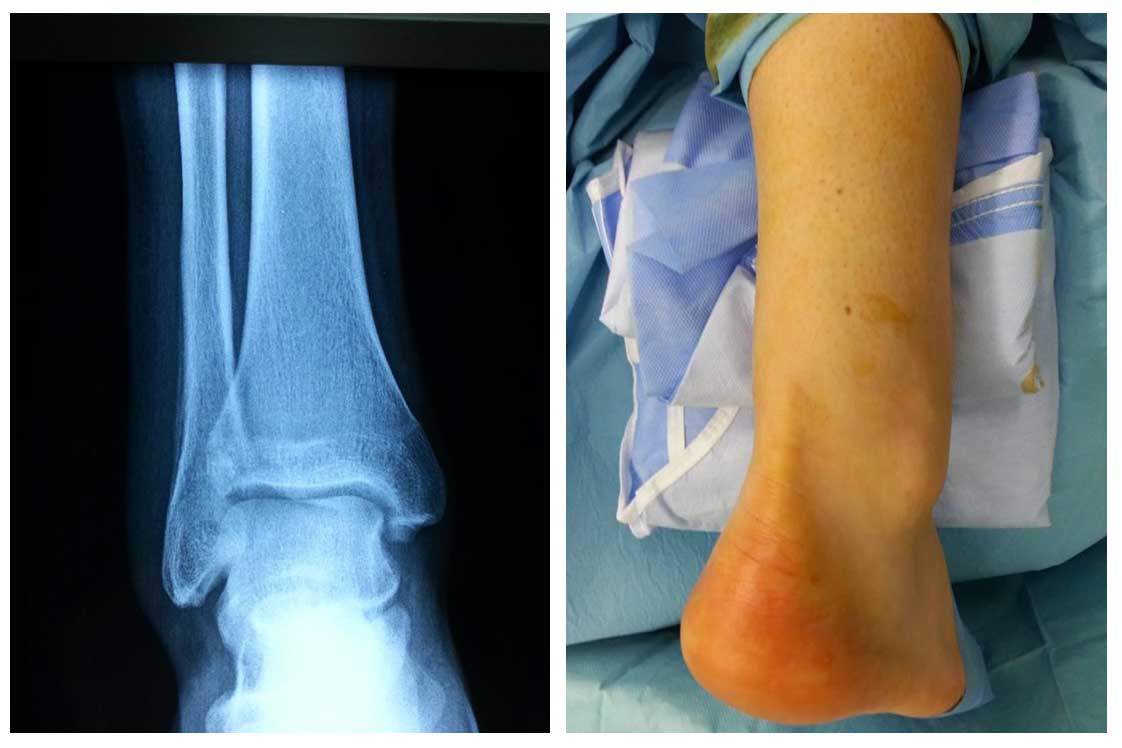

Ameliyat Öncesi: Röntgende distal fibula lateralde periost reaksiyonu ve klinik olarak aynı bölgede şişlik görülmekte.